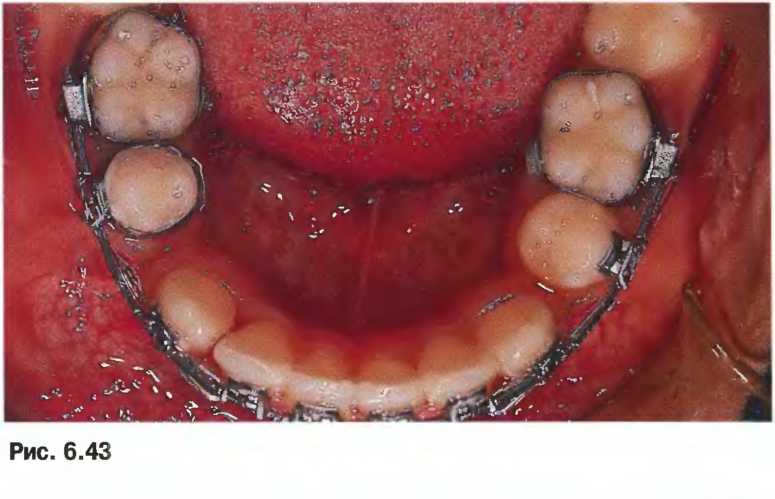

Пациент на позднем этапе сменного прикуса с нормальным развитием всех постоянных зубов. Отмечается некоторая скученность нижних зубов и смещение верхней срединной линии на 2 мм вправо. Предполагали, что коррекцию зубов можно выполнить без удаления зубов. Однако, для ретракции резцов и улучшения профиля лица принято решение удалить все четыре первые премоляры и выполнить лечение с максимальной фиксацией. На начальном этапе лечения установлены нёбная дуга на верхней челюсти и язычная дуга на нижней челюсти. Для достижения целей лечения в ночное время пациент использовал внеротовую тягу (headgear).

Выравнивание и перемещение зубов начато термоактивируемыми никелево-титановыми дугами диаметром 0,016 дюйма, затем аналогичными прямоугольными дугами. На данном снимке представлен этап лечения с прямоугольными стальными дугами и пассивными связками tieback до начала коррекции горизонтального и вертикального прикуса и закрытия промежутков.

На вторые нижние премоляры (с. 136) зафиксированы кольца для улучшения коррекции кривой Шпее на нижней челюсти. На снимке представлена ситуация после 16 месяцев лечения. Кольца на первых нижних премолярах репозиционированы.